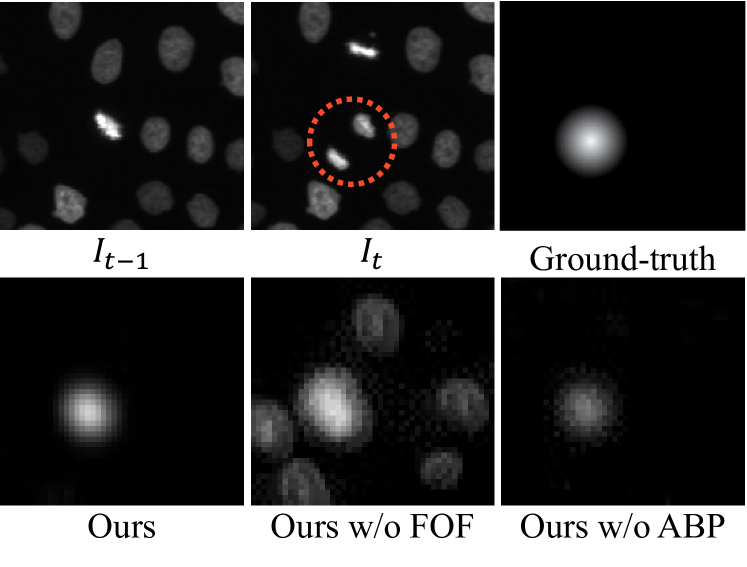

Table 2: Ablation study. FOF: frame-order flipping, ABP: alpha-blending pasting.

Method F1

w/o FOF 0.570

w/o ABP [23] 0.670

Ours 0.795

Effectiveness of each module: We performed an ablation study on the HeLa dataset to investigate the effectiveness of the proposed module. We used random augmentation (i.e., random elastic transformation [17], brightness change, and gaussian noise) instead of using frame-order flipping (FOF). We generated 𝑰taugsuperscriptsubscript𝑰𝑡𝑎𝑢𝑔\bm{I}_{t}^{aug} by augmenting 𝑰tsubscript𝑰𝑡\bm{I}_{t} and input the pair (𝑰t,𝑰taug)subscript𝑰𝑡superscriptsubscript𝑰𝑡𝑎𝑢𝑔(\bm{I}_{t},\bm{I}_{t}^{aug}) to the network. In the w/o ABP setting, we directly pasted cropped images on the target image as in CutMix [23]. Table 7 demonstrates that the proposed modules improve mitosis detection performance. Fig. 9 shows examples of the estimation results for each condition. Without the FOF setting, the detection model estimates a high value for all moving cells, leading to over-detection. Without the ABP setting, the detection model overfits the directly pasted image. The directly pasted image tends to include unnatural boundaries on the edge, leading to missed detections in real images.